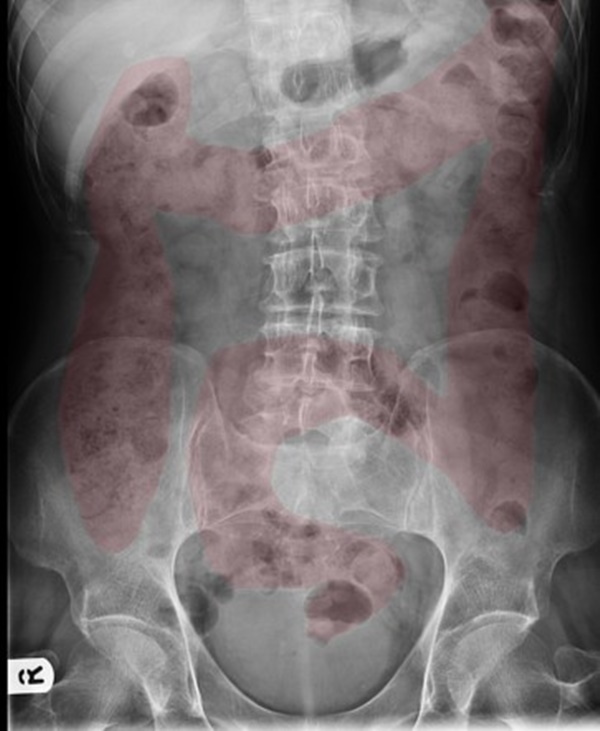

Bác sĩ đã cho bà mẹ xem hình ảnh chụp X-quang ổ bụng của con gái bà, chỉ ra rằng ruột già đã bị chặn bởi phân và đó là lý do vì sao cô bé lại phải đối mặt với những cơn đau bụng dữ dội. Bác sĩ cho biết trước đây cũng từng gặp một số trường hợp tương tự ở những đứa trẻ cùng tuổi.

Hình mang tính minh họa.